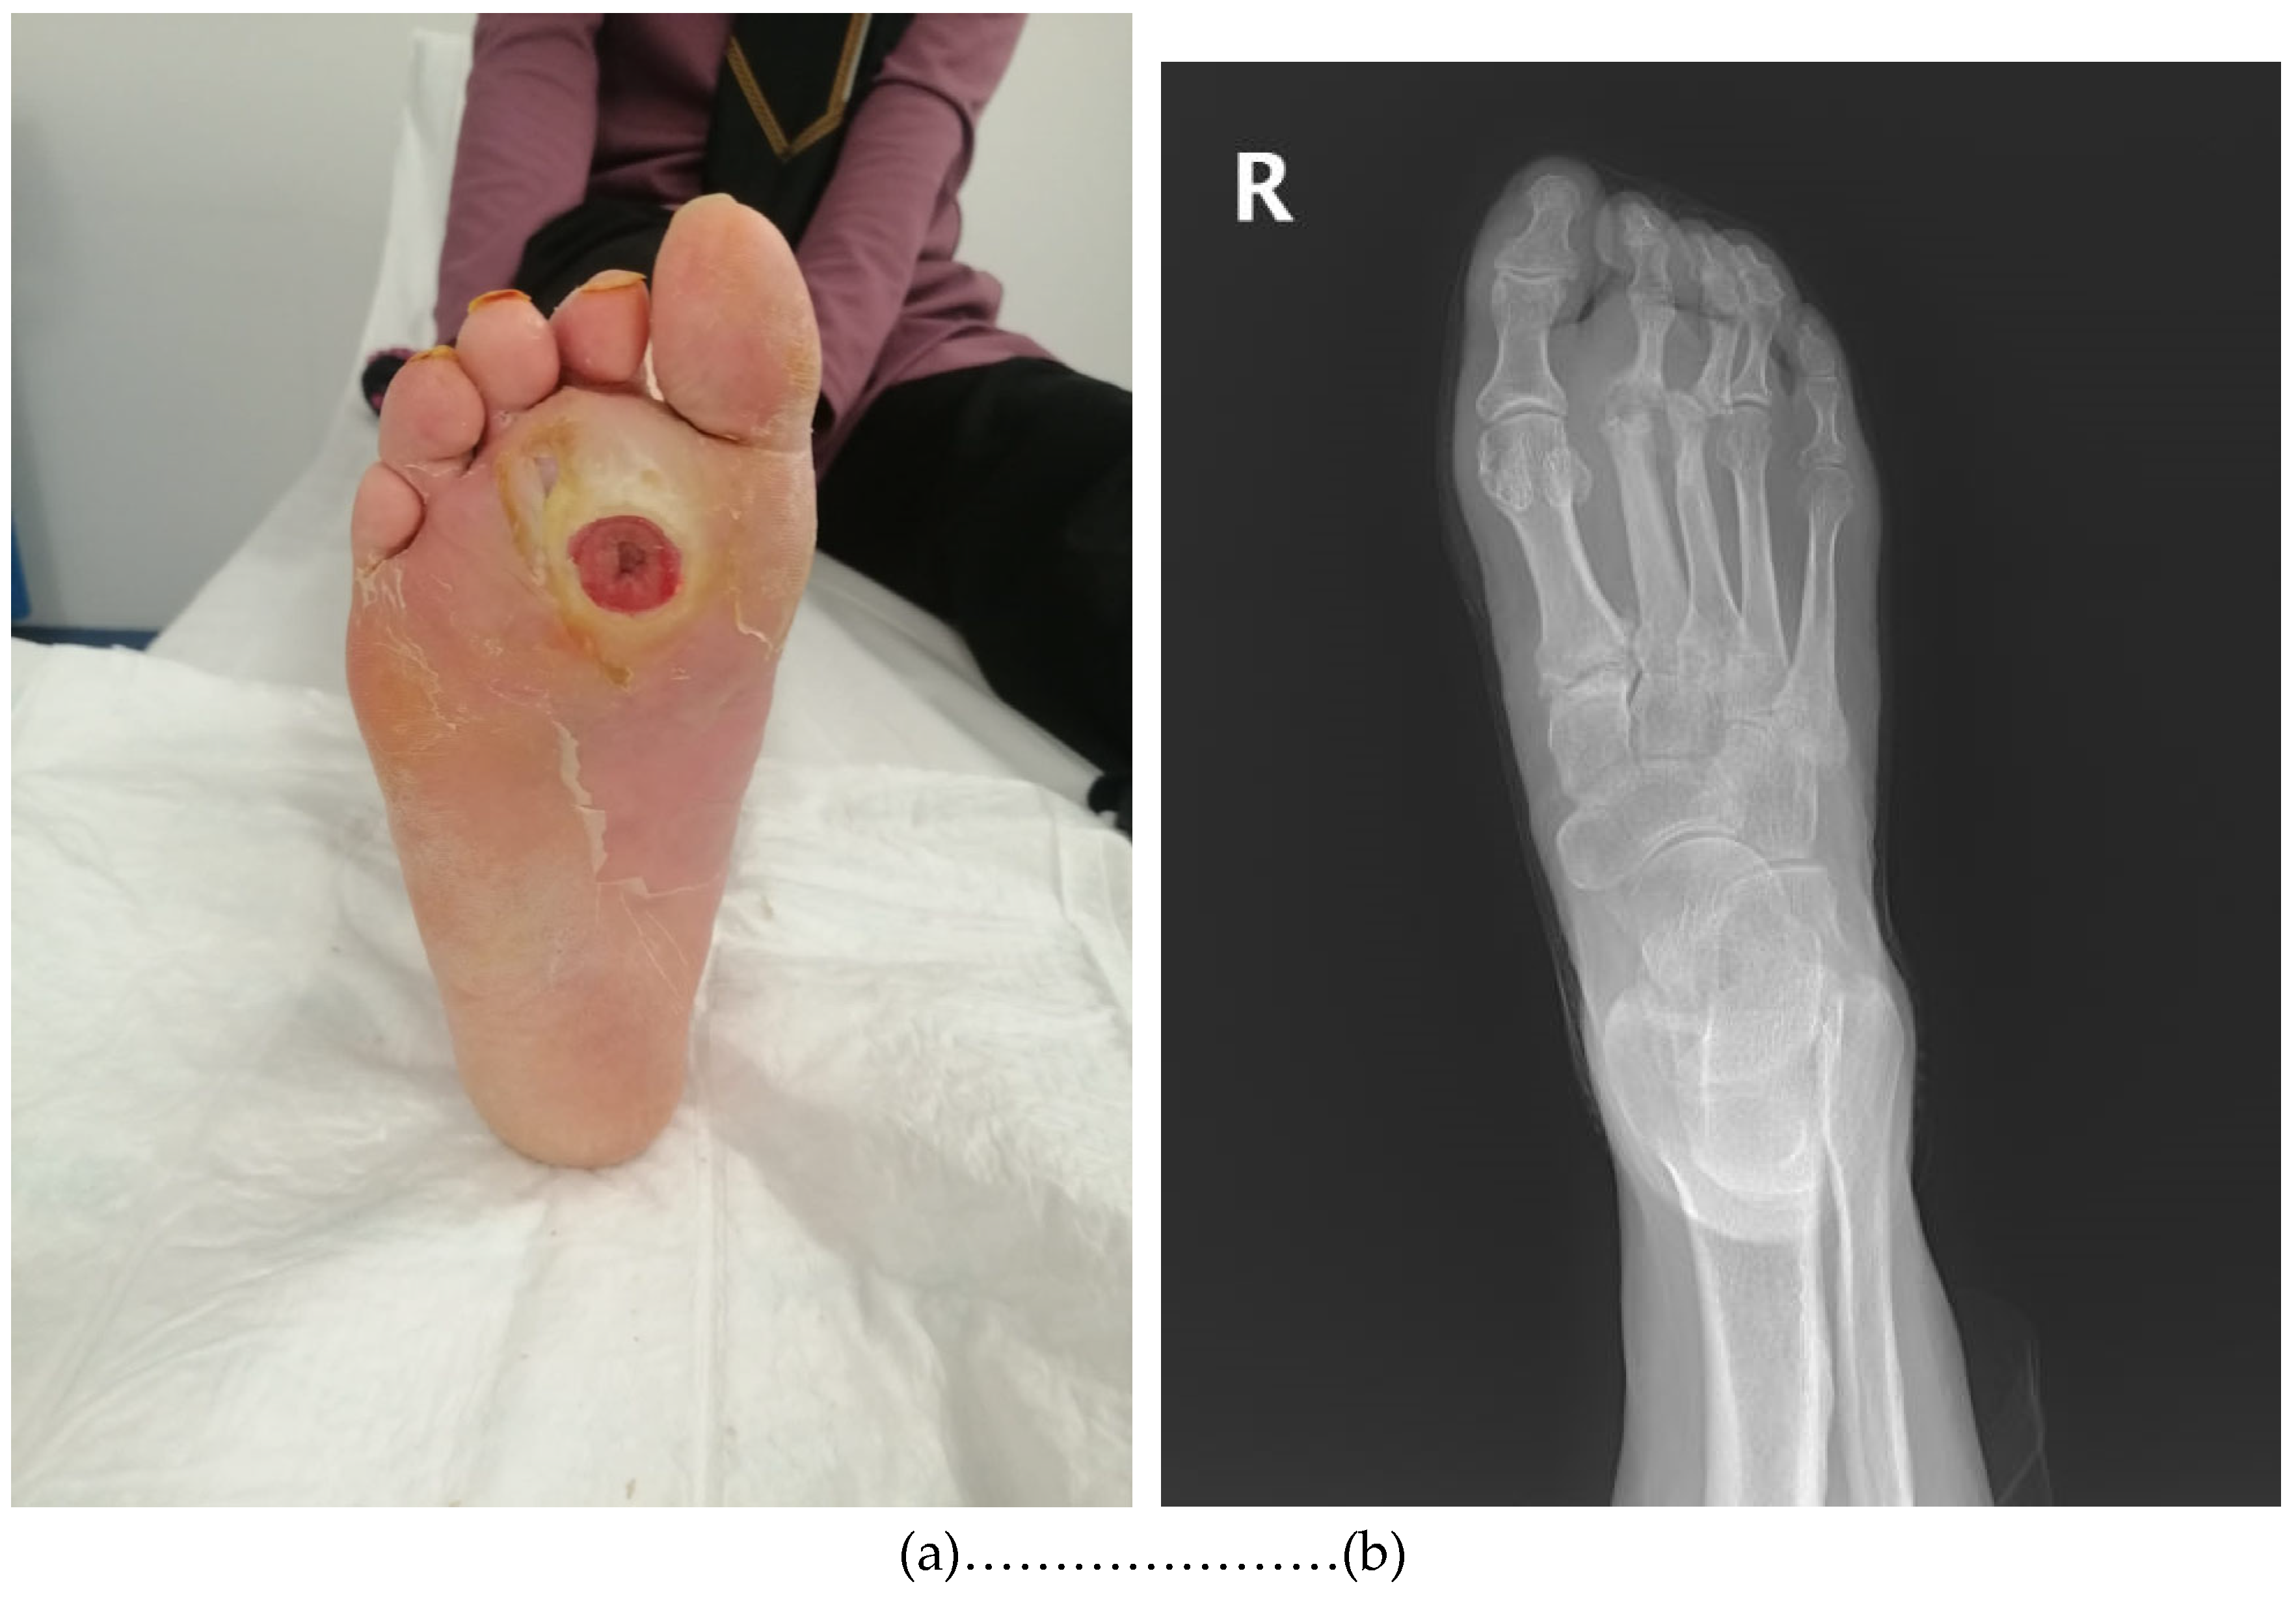

- Positive probe-to-bone (PTB) test (performed using a sterile blunt metal probe; considered positive when bone was palpable through the ulcer);

- Radiographic evidence of osteomyelitis (presence of suggestive findings in initial or follow-up X-rays);